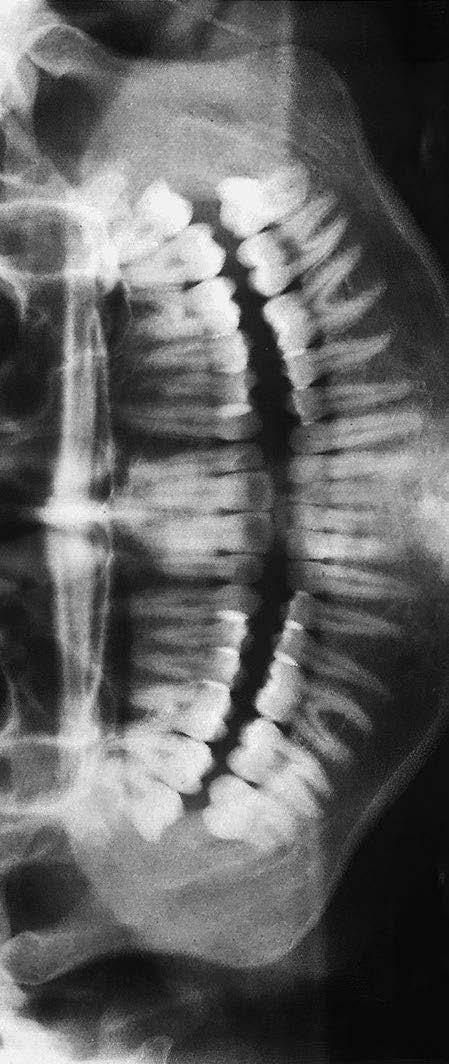

1 articulatio temporomandibularis (čelistní kloub)

2 caput mandibulae (hlavice dolní čelisti)

3 processus coronoideus (krkavčitý výběžek)

4 alveolární okraj

5 foramen mandibulae

6 protuberantia mentalis (bradový výběžek)

7 cavitas dentis (pulparis) (dřeňová dutina zubu)

8 canalis radicis dentis (zubní kanálek)

9 foramen apicis radicis dentalis

10 foramen mentale

11 canalis mandibulae (kanál v dolní čelisti)

12 angulus mandibulae (úhel dolní čelisti)

1 stříška kloubní jamky čelistního kloubu

2 articulatio temporomandibularis (čelistní kloub)

3 caput mandibulae (hlavice dolní čelisti)

4 sinus maxillaris (dutina horní čelisti)

5 cavitas nasi (nosní dutina)

6 processus coronoideus (krkavčitý výběžek)

7 maxilla (horní čelist)

8 ramus mandibulae (rameno dolní čelisti)

9 angulus mandibulae (úhel dolní čelisti)

10 dentes molares (stoličky)

12 dentes premolares (premoláry)

13 dens caninus (špičák)

14 dentes incisivi (řezáky)

15 foramen mentale

16 tuberculum mentale (sumace s projasněním trachey)

19 canalis radicis dentis (kořenový kanál)

20 cavitas dentis (pulparis) (dřeňová dutina zubu)

21 dentin korunky (zubovina)

22 sklovina 23 foramen mentale

24 radix dentis (zubní kořen)

25 dentes incisivi (řezáky)

26 dens caninus (špičák)

27 dentes premolares (premoláry)

28 dentes molares (stoličky)

10 recessus alveolaris (dno dutiny horní čelisti) 11 sinus maxillaris (dutina horní čelisti) 12 fossa pterygopalatina 13 processus pterygoideus (křídlový výběžek kosti klínové) 14 angulus mandibulae (úhel dolní čelisti) 15 stín jazyka 16 canalis mandibulae (kanál v dolní čelisti) 17 os hyoideum (jazylka) 18 foramen apicis radicis dentis